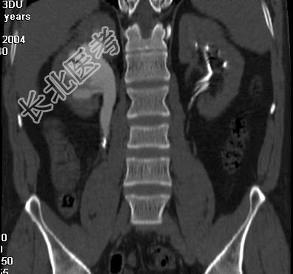

- 多项选择题患者男,36岁, 反复发作的右侧腰背部疼痛伴血尿1年余加重2小时,CT如图所示, 下列说法正确的是 ( )

A、右侧肾盂肾盏扩张

B、右输尿管上段扩张

C、右输尿管内可见沿输尿管走行的高密度影

D、右输尿管结石

E、右输尿管上段钙化